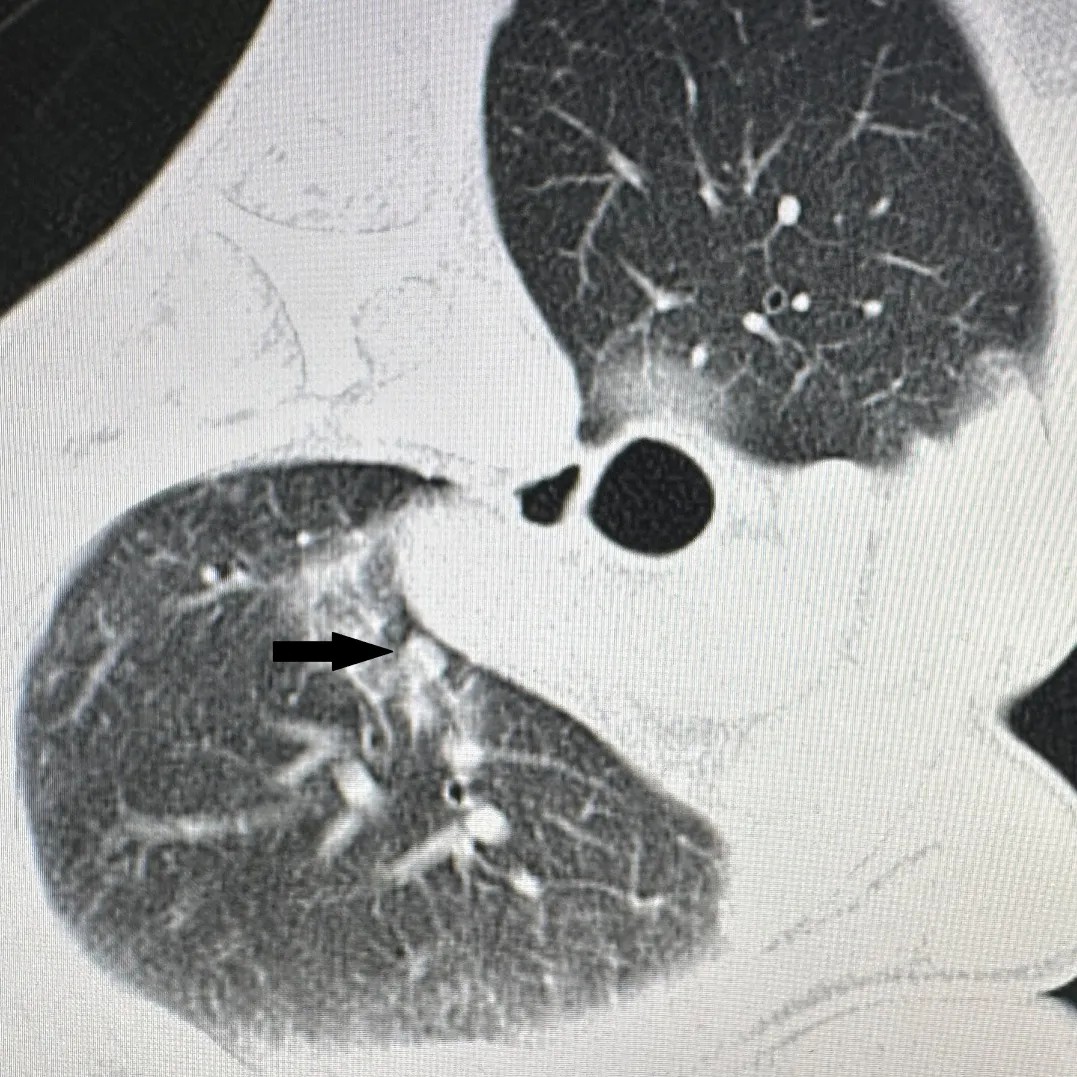

(黑色箭头)

消融术后肿瘤完全坏死

胸部CT显示肺上病灶一个位于肺上叶,因病灶位置较高,肋间隙较窄,比邻肩胛骨,给穿刺造成明显困难;另一个病灶紧邻主肺动脉,穿刺出血风险极高。7月25日,李建军主任经过仔细读片,认真分析,选择了最佳的穿刺路径,通过CT引导,在次旺晋美医师辅助,扎西次仁和德吉卓嘎护士配合下,一次手术对两个病灶进行了精准消融,术后CT扫描显示病灶完全坏死,未出现气胸等并发症,患者安返病房。